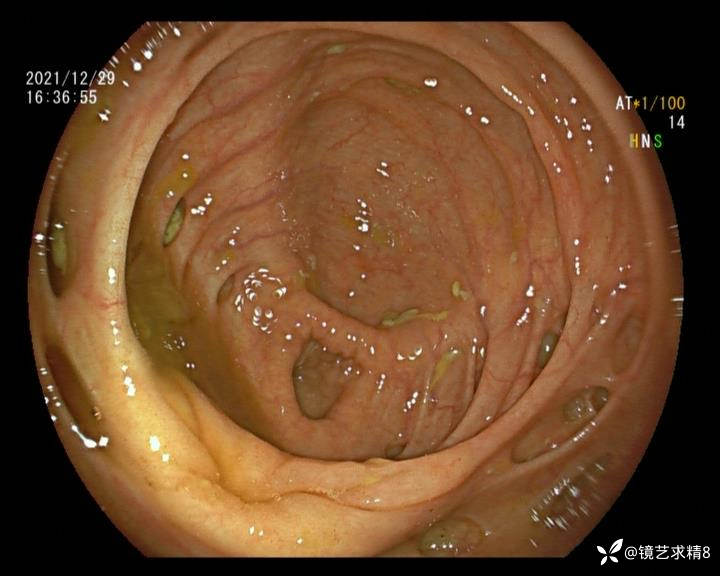

结肠内违建⥤结肠多发憩室☞续

小壮兵爱学习等 2人推荐看到手机存有2年前一个病例仅有的3张图片,因为没有更多的图片就只描述了多发憩室这个内容,没想到浏览量很快上万,很多都和我一样第一次见这么多憩室的结肠,就不得不想要把2年前所有的片子拷贝出来分享。该病例憩室合并外源性因素成为憩室出血的原因。后面附有代表性的全结肠图片。

患者以消化道出血入院,胃镜未见异常,肠镜进入乙状结肠就看到很多憩室,同时还看到肠腔用清肠药后移动下来1枚尖锐的枣核,这么多憩室,这个枣核扎入憩室的机会非常大,推测应该是掉入一坑🕳就算出来还会有很多坑🕳🕳🕳等着,掉入憩室内很容易刺破血管,这可能就是消化道出血的原因,继续前进可以看到有一些憩室内翻,还有一些息肉,问题来了,那么多憩室,犯罪分子是抓住了,它在那些憩室内作过案?到达回盲部后挨个冲洗,但憩室大小又不足以把镜头进入憩室内观察,针对有血块的憩室冲洗后可疑出血的以夹子闭合或套扎,取出枣核,如果有锥形透明帽可能钻入憩室精准电凝效果更好,若内镜下操作失败介入治疗成功率更高,经内镜下治疗后观察未再出血出院。